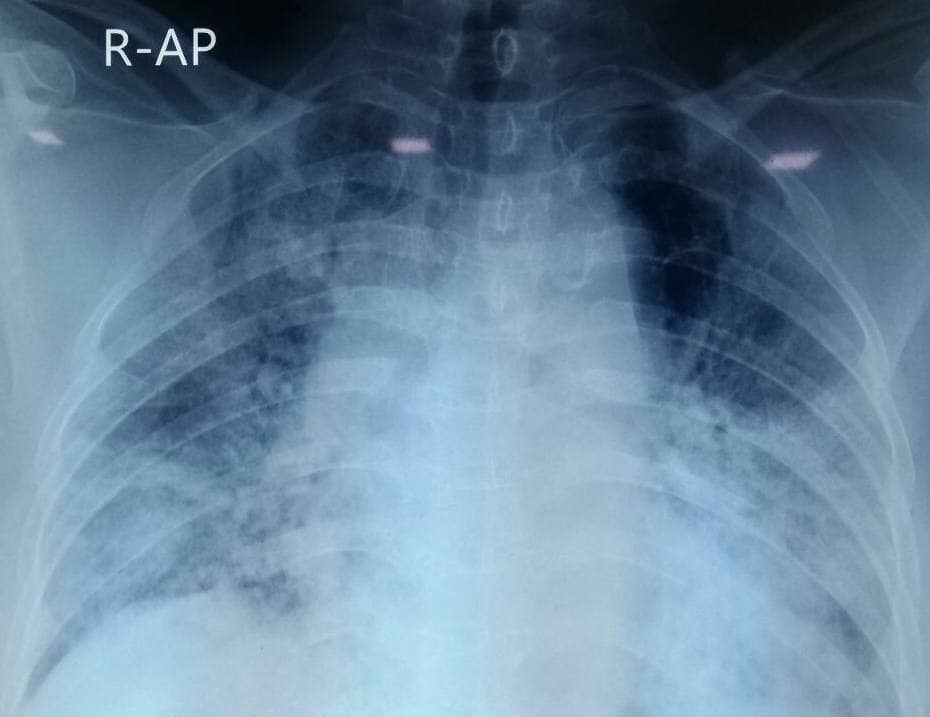

“មានបទពិសោធន៍ជាង1ឆ្នាំក្នុងគ្រប់គ្រង និងព្យាបាលជំងឺកូវីដដោយគ្មានការភ័យខ្លាចឬតក់ស្លុតឡើយ ។ តែក្នុង1ខែចុងក្រោយនេះចាប់ពី 20 កុម្ភៈ 2021 ខ្ញុំមានអារម្មណ៍ភ័យខ្លាច និងព្រួយបារម្ភណាស់ ពីព្រោះវាជាប្រភេទមេរោគប្រែរូបថ្មី (variant virus strain) ដែលក្នុងរយៈពេលតែ2ទៅ5ថ្ងៃវាវាយលុកចូលសួតធ្វើអោយរលាកធ្ងន់ធ្ងរទាំងសងខាង ។ រូបភាពសួតត្រូវបានមេរោគស៊ីសុះសាច់ដ៏គួអោយខ្លាច ។